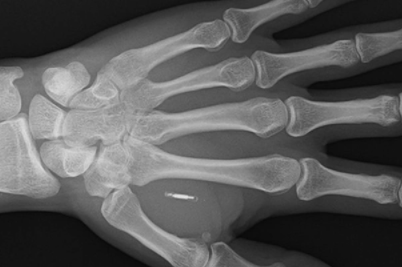

“这是因为这位37岁的老人不需要使用银行卡或手机支付。相反,他只需将左手放在非接触式读卡器附近,即可完成付款。“我从收银员那里得到的反应是无价的!”来自荷兰的保安Paumen先生说。他能够用手支付,因为早在2019年,他的皮肤下就注射了一个非接触式支付微芯片。“这个过程就像有人捏你的皮肤一样疼,”波门先生说。